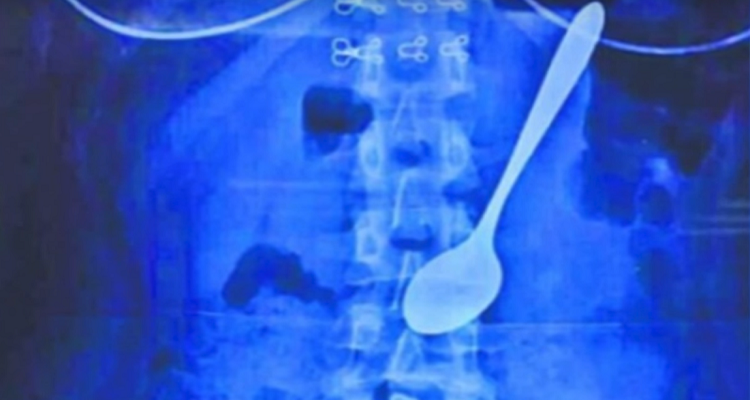

استطاع أطباء من مقاطعة "شينجيانغ" الصينية إنقاذ شاب كان قد ابتلع ملعقة طعام وعاش وهي بداخله عاما كاملا.

وذكر موقع ديلي ميل أن الشاب البالغ من العمر 26 عاما قدم إلى أحد مشافي المقاطعة مشتكيا من آلام في البطن وصعوبة في التنفس، وبعد معاينته، اكتشف الأطباء أن ملعقة طعام عالقة في المريء أسفل حلقه.

وبعد استجواب المريض، أخبر الأطباء أنه ومنذ نحو عام كان قد ابتلع الملعقة بالخطأ عندما كان في حالة سكر، وبقيت الملعقة بداخله طول تلك الفترة.

وقام الأطباء باستخراج الملعقة من داخل المريض عبر الفم، لكنهم ذكروا أنه سيخضع للعلاج بسبب الجروح والتقرحات التي أصابته في المريء.